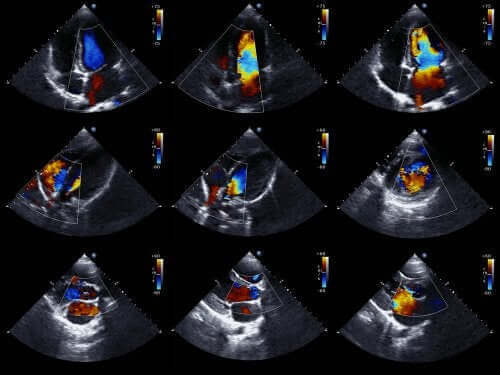

Artsen kunnen meestal dit soort anomalieën vaak al diagnosticeren voordat een baby wordt geboren. Om dit te doen, gebruiken ze een foetaal echocardiogram. Dit is een techniek die geluidsgolven gebruikt om een bewegend hartbeeld te reproduceren en een van de meest effectieve technieken om aangeboren hartproblemen te diagnosticeren.

Dankzij dit onderzoek kunnen we het uiterlijk van het hart zien en de werking ervan al onderzoeken wanneer een foetus zich nog in de baarmoeder bevindt. Met deze informatie kunnen artsen maatregelen nemen om onmiddellijk na de geboorte de behandeling uit te kunnen voeren.